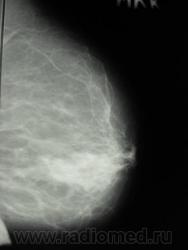

пациентка после травмы молочной железы, с 26.02.09 предъявляет жалобы на кровянистые выделния из правого соска. Осмотрена онкологом- посттравматическая гематома правой молочной железы, ПАБ материал получен из очага кровоизлияния. Делала мамографию, заключение из другой больницы- узловая фиброзная мастопатия правой молочной железы. А на УЗИ- дилятация мелких протоков в правой молочной железе, склерозированный лимфоузел в наружной области справа 11 на 5 мм. На данный момент беспокоят все те же выделения из правого соска, напрвили к нам на маммографию, боятся онкологию пропустить. Ваше мнение коллеги?

последние 3 снимка-архив 28.05.09 г. Женщина 1935 г.р.

И вот, вышло такие две серии:

А, ведь, какая-то "объёмка" вырисовывается.